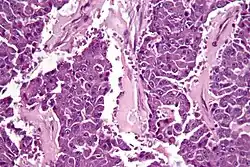

Pancreatic cancer cells

This type of collagen can cause an increase in pancreatic cancer cells and is able to inhibit apoptosis through an autocrine loop.[4]

This autocrine loop provides essential cell survival signals to the pancreatic cancer cells.[4]

Type IV collagen is expressed close to the cancer cells in vivo, forming basement membrane like structures on the cancer cell surface that colocalize with the integrin receptors. The interaction between type IV collagen produced by the cancer cell, and integrins on the surface of the cancer cells, are important for continuous cancer cell growth, maintenance of a migratory phenotype, and for avoiding apoptosis.[4]

Pancreatic cancer cell in high magnification